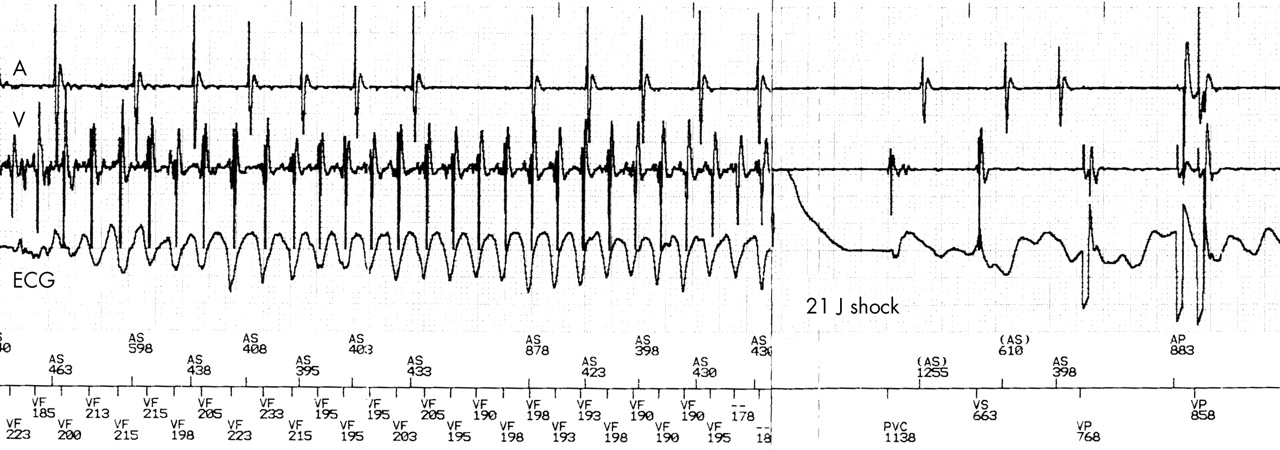

Implantable Cardioverter Defibrillator (ICD)

ICD_shock.jpg

ICD - 20 to 30% reduction in deaths